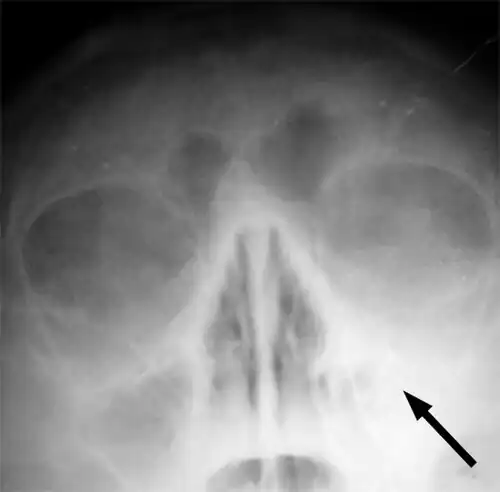

Imaging by either X-ray, CT, or MRI is generally not recommended unless complications develop.[66] Pain caused by sinusitis is sometimes confused for pain caused by pulpitis (toothache) of the maxillary teeth, and vice versa. Classically, the increased pain when tilting the head forwards separates sinusitis from pulpitis.[68]

-

Maxillary sinusitis caused by a dental infection associated with periorbital cellulitis -

Frontal sinusitis -

X-ray of left-sided maxillary sinusitis marked by an arrow. There is a lack of air transparency, indicating fluid in contrast to the other side.